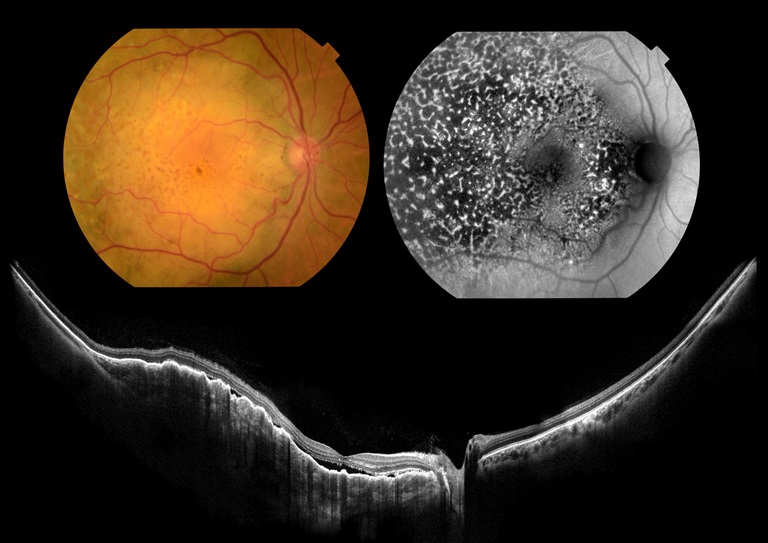

Leopard Skin Retinopathy

Presented by Sousa Jefferson, BEng, COMTThis photograph received Honorable Mention in the category "Cross Categories" and was displayed at the 2024 ASCRS/OPS Society Exhibit.